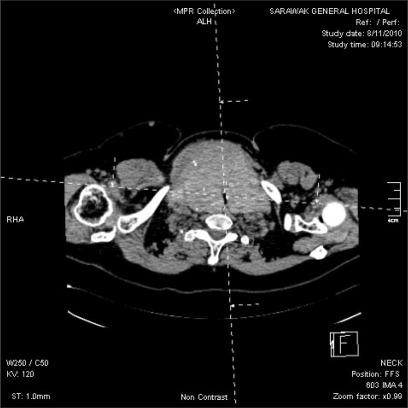

Anesthetic management of patients with mediastinal masses remains challenging as acute cardiorespiratory decompensation may follow induction of anesthesia. We describe a 57 year old lady with massive retrosternal goiter and severe intrathoracic tracheal compression who had a total thyroidectomy. Comprehensive contingency plans were an essential prerequisite for successful management of difficult airway, including multidisciplinary involvement of otorhinolaryngologic and cardiothoracic surgeons preparing for rigid bronchoscopy and cardiopulmonary bypass. Awake oral fiberoptic intubation was performed under dexmedetomidine sedation. Severe tracheal narrowing necessitated usage of a 5.0 mm uncuffed flexometallic endotracheal tube. Anesthesia was maintained with sevoflurane and dexmedetomidine infusion with target controlled infusion of remifentanil as analgesia. No muscle relaxant was given. Surgical manipulation led to intermittent total tracheal compression and inadequate ventilation. The tumor was successfully removed via the cervical approach. A close working relationship between anesthesiologists and surgeons was the key to the safe use of anesthesia and uneventful recovery of this patient.

纵隔肿块患者的麻醉管理仍然具有挑战性,因为麻醉诱导后可能会出现急性心肺代偿失调。我们描述了一位 57 岁的女性,患有巨大胸骨后甲状腺肿和严重的胸腔内气管压迫,需要进行全甲状腺切除术。为了成功管理困难气道,包括耳鼻喉科和心胸外科医生多学科参与准备硬质支气管镜检查和体外循环,综合应急计划是必不可少的前提条件。在右美托咪定镇静下进行清醒经口纤维光导插管。严重的气管狭窄需要使用 5.0 毫米无套囊 Flexometallic 气管内导管。麻醉维持使用七氟醚和右美托咪定输注,并使用瑞芬太尼靶控输注作为镇痛。未给予肌松剂。手术操作导致间歇性完全气管压迫和通气不足。肿瘤通过颈部入路成功切除。麻醉师和外科医生之间的密切合作关系是安全使用麻醉和使该患者顺利恢复的关键。